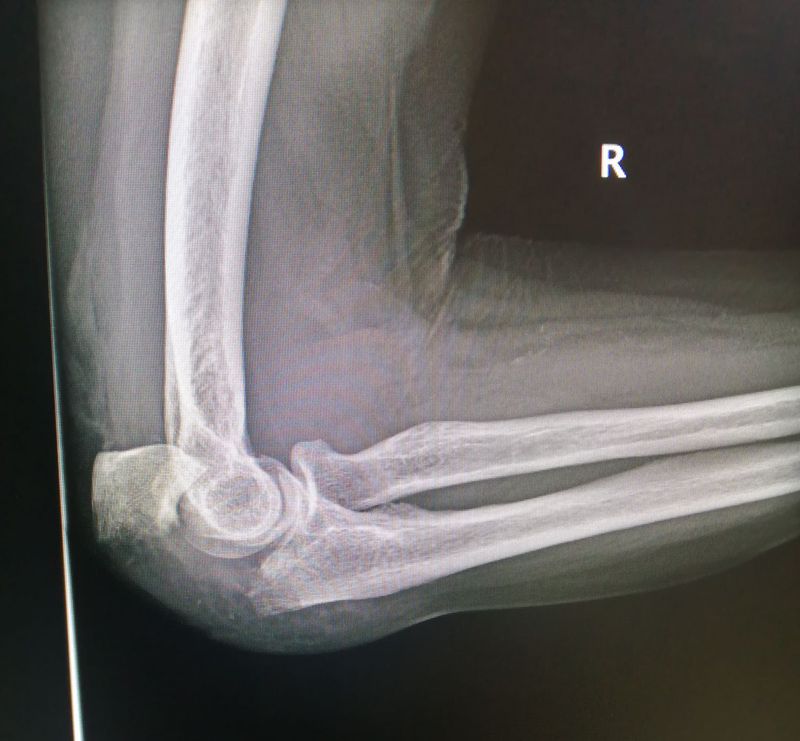

Elbow LAT view

Olecranon Fracture

Right

Elbow

Olecranon